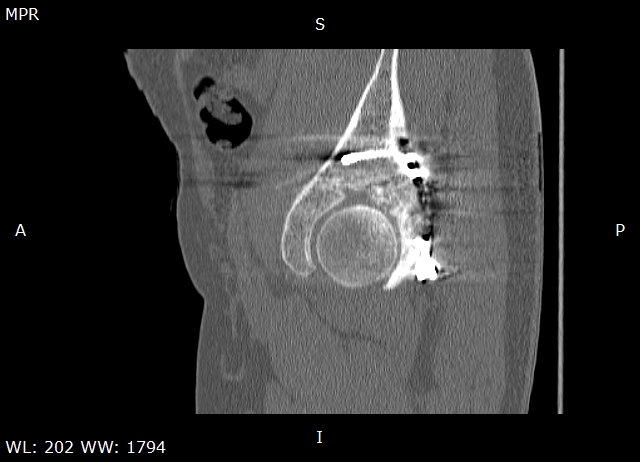

Травма в 2015 году. Водитель, попал в ДТП. Первично повреждение печени, перелом локтевой кости слева. Перелом задней колонный и задней стены левой вертлужной впадины. По экстренным показаниям выполнялась лапаротомия. Синтез задней колонны и задней стены через 13 дней через доступ Кохера-Лангенбека. Гладкий послеоперационный период. Выписан на амбулаторное лечение через 15 дней после операции. После выписки к нам не обращался, так как является жителем другого региона. Обратился через 2,5 года с жалобами на боли в области левого тазобедренного сустава.

На РКТ таза - перелом сросся. Отмечается кисты в области верхнего полюса головки бедра. Пластина фиксирующая задний край соприкасается с задними отделами головки бедра (видимо произошел частичный лизис костного края).

У пациента посттравматический коксартроз 2ст. Учитывая невыраженный болевой синдром лучше ограничиться удалением металлоконструкции. Головка не деформирована кисты относительно небольшого размера - продолжить консервативное лечение с ограничением нагрузок занятий спортом. Упражнения для сохранения мышц и объема движений, бассейн.